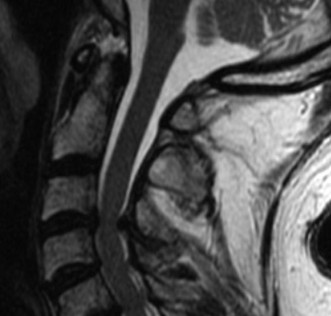

Recognize surgical and nonsurgical indications for a thoracic lymphoma? Definitively manage a thoracic lymphoma? CASE 13 A 23-year-old man was involved in a high-speed motor vehicle accident. On presentation to the trauma bay, his chief complaint was neck pain. Physical examination demonstrated that he was neurologically intact. Images of the cervical spine are shown in Figure 1–19A–B. Full workup demonstrated no other injuries.

Figure 1–19 A–B

The correct answer is (B). The imaging clearly demonstrates a Hangman’s fracture, also known as a C2 traumatic spondylolisthesis. The hallmark of this injury is a fracture through the pars interarticularis of C2, which effectively dissociates the anterior elements from the posterior arch and facet joints. A Jefferson fracture refers to C1 ring fractures that can have varying degrees of lateral displacement. There is no evidence of vertebral body comminution with posterior vertebral body involvement, which would be characteristic of a burst fracture. While some Hangman’s fractures can be associated with facet dislocation, there is no evidence of this on the imaging.

The correct answer is (B). Type I fractures have minimal horizontal displacement, no angulation, and the C2–3 disc remains intact. Type II fractures are both displaced and angulated, presumably hinging around the anterior longitudinal ligament. Importantly, these fractures reduce with longitudinal traction. Type IIA fractures have minimal horizontal displacement but are significantly angulated. It is presumed that the anterior fragment rotates in place, most likely disrupting the anterior longitudinal ligament. These injuries are worsened by traction and reduced with axial compression. Type III fractures have bilateral C2–3 facet dislocations.